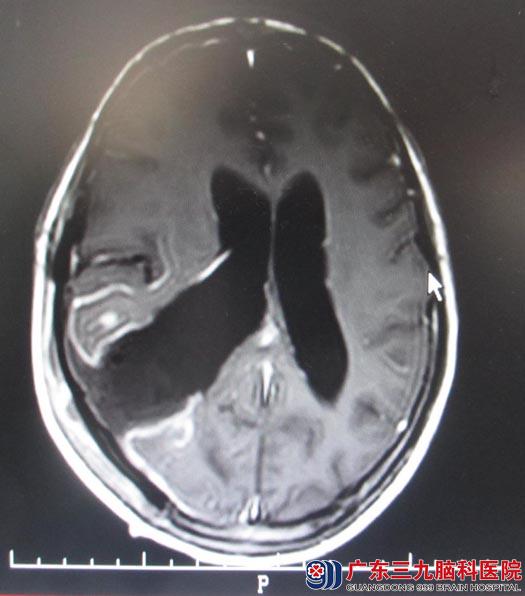

四月份曾在广东三九脑科行颅脑MR检查,示:右侧侧脑室三角区巨大占位性病灶,考虑肿瘤性病变。后入住综合神经外科,复查颅脑MR显示:1、右侧侧脑室三角区及周围巨大占位病灶,大小约7cm×9cm,考虑室管膜瘤、中枢神经细胞瘤或PNETs(原始性神经外胚层瘤)可能;2、右侧大脑镰下疝,右侧海马钩回疝,小脑扁桃体轻度下疝;3、空泡蝶鞍。肿瘤挤压对侧脑室,中线左移。

5月14日,由综合神经外科鲁明主任主刀,取右侧额颞顶马蹄形切口,从右颞叶皮层造瘘,皮层下见灰白色肿瘤组织,肿瘤质地中,血供丰富,边界较清,从肿瘤边缘蛛网膜小心分离,超声刀下分块将肿瘤全切。术后钟女士恢复良好,无头痛、头晕,可下床自主活动。病理结果:过渡型脑膜瘤(WHO1级)。